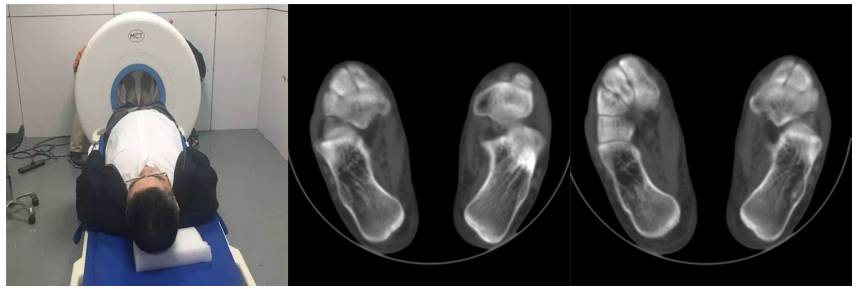

16层移动CT足部扫描